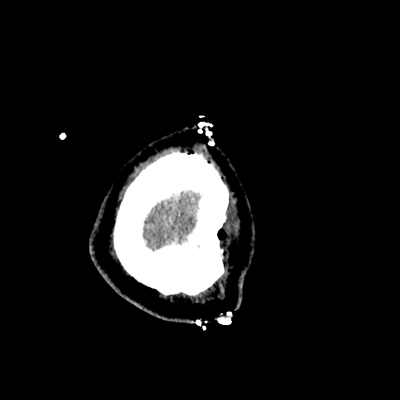

On day 5 of admission, he begins having intracranial hypertension again, spiking up to 40mmHg. You bolus with propofol and fentanyl, to no avail. You then push 30mL of 23.4% NaCl, which provides some brief improvement, allowing you to quickly get a non-contrast head CT. Unfortunately, he's now back up to 36mmHg. You review his labs, and note the following: Na 150, K 3.8, Cl 119, HCO3 18, BUN 21, Cr 0.85, glucose 136, sOsm 320.

NCHCT

NCHCT 3/20 3/20